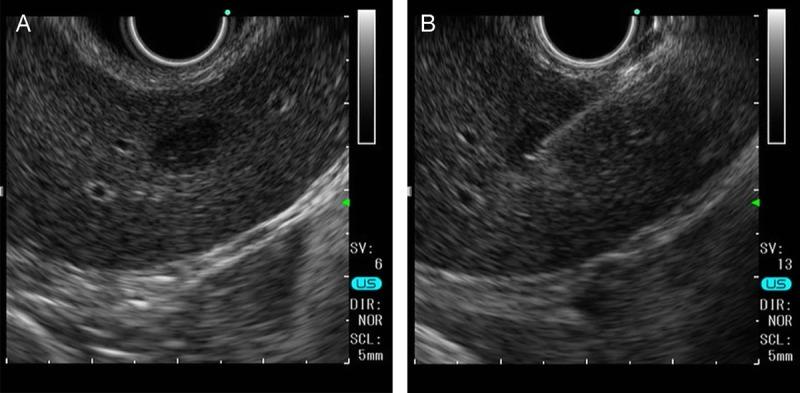

A suspected case of hepatic reactive lymphoid hyperplasia in which EUS-fine needle aspiration contributed to the diagnosis.

Endosc Ultrasound. 2024 Nov-Dec;13(6):379-381. doi: 10.1097/eus.0000000000000092. Epub 2024 Dec 30.